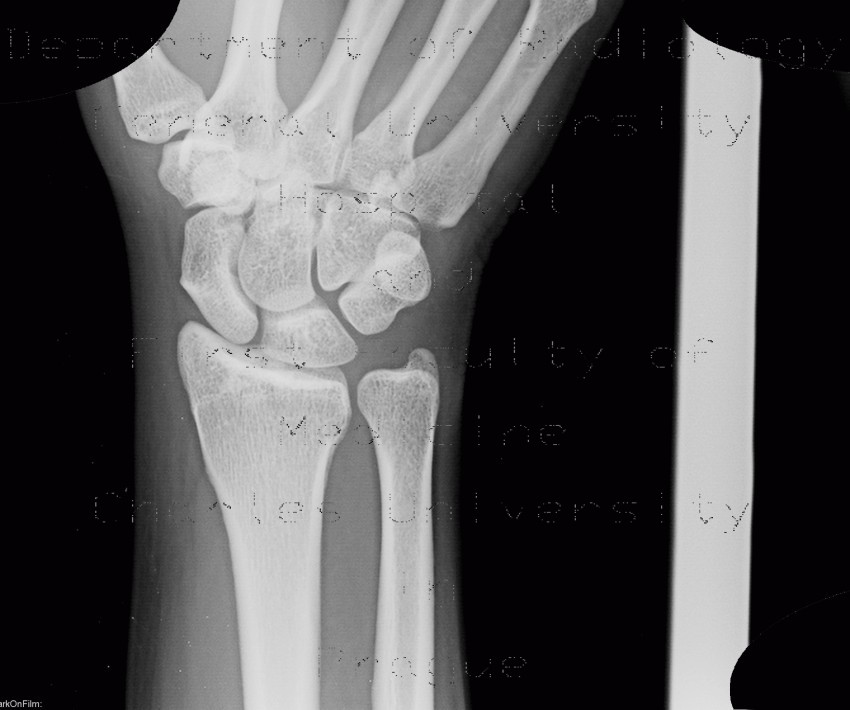

Ap x ray of wrist. Radiograph of the thumb. Trace these arcs on the ap film. Some pathologic processes such as osteomyelitis and arthritis also maybe seen. Normal wrist x ray in an adult female for reference.

See approach to wrist series for more information. X rays of the wrist joint are requested frequently particularly at the emergency assistance department. The wrist and elbow should be at shoulder height which makes radius and ulna parallel lowering the arm makes radius cross the ulna and thus relative shortening of radius. Mri of the shoulder.

The standard wrist views are posterior anterior pa and lateral. The spacing between all carpal bones should be 1 2 mm. The wrist comprises the scaphoid lunate triquetrum pisiform trapezium trapezoid capitate and hamate bones. The affected hand is placed palm down on the image receptor.

They are used primarily to confirmexclude a fracture in the diagnostics of rheumatoid arthritis and in functional hand and wrist symptoms. The academic rule of a true lateral wrist radiograph is defined by the pisoscaphocapitate relationship where the palmar cortex of the pisiform should lie centrally between the anterior surface of the distal pole of the scaphoid and the capitate ideally in the central third of this interval 1. The wrist series is comprised of a posteroanterior oblique and lateral projectionthe series examines the carpal bones that are consisting of the scaphoid lunate triquetrum pisiform trapezium trapezoid capitate and hamateit also examines the radiocarpal and distal radiocarpal joint along with the distal radius and ulna. Shoulder elbow and wrist should all be in the transverse plane perpendicular to the central beam.

The radiocarpal distal radioulnar and carpometacarpal joints can also be considered part of the wrist. Ct of the wrist. Wrist hand and fingers. An x ray wrist with both ap and an oblique view is helpful in finding the cause of behind the signs and symptoms of pain tenderness swelling and deformities of the wrist joint.